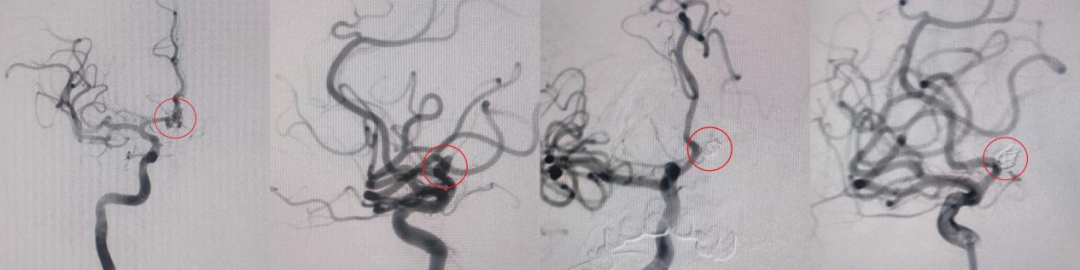

49岁女性,近期23点半因突发头痛伴恶心2小时就诊,CT提示蛛网膜下腔出血。神经外科会诊后明确诊断:前交通动脉瘤破裂(此次责任动脉瘤)及左侧颈内动脉眼动脉段未破裂动脉瘤。黄宪团队综合评估后,决定连夜实施急诊手术先处理破裂动脉瘤,待病情稳定后再处理未破裂病灶。手术连夜顺利完成,患者术后恢复良好,一个月后状态稳定,再次入院接受血流导向装置置入术处理另一动脉瘤。分期治疗策略有效降低了单次手术创伤与风险,这种“先救急、再治缓”的策略,缩短了手术时间、降低了术中血管痉挛、血栓形成等并发症风险,同时避免了急性期口服抗血小板药物治疗带来的潜在风险。

图3:左侧颈内动脉眼动脉段动脉瘤支架辅助栓塞术中过程、术后造影

62岁女性,因突发头痛、头晕从电动三轮车上摔倒,当地医院CT示脑出血后紧急转送我院急诊。我科全面评估后,确诊为基底动脉动脉瘤破裂合并脑出血。考虑到单纯介入或开颅手术均难以兼顾动脉瘤闭塞与血肿引流,李春浩团队决定采用复合术式:先在介入室实施单纯弹簧圈栓塞(未放置支架,避免口服抗血小板药物带来后期手术出血的风险,提升手术安全性),精准闭塞基底动脉动脉瘤后行脑室钻孔引流术,及时清除颅内血肿、降低颅内压。术后患者安返重症医学科,2日后转入普通病房,恢复顺利,实现具体疾病具体诊治。

图4基底动脉动脉瘤介入栓塞术后造影及三维成像